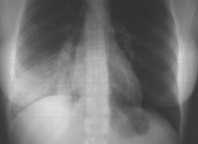

L’Rx del torace evidenzia un addensamento parenchimale che occupa la base di destra (Figure 1-2) con modesto versamento (ecografia: pochi millilitri). Indici di flogosi elevati (VES 52, PCR 17 mg/dL. GB 6.600, N73%, L11%, M15%, E1%, Plt 90.000). Emocultura negativa; ricerca di antigeni batterici nelle urine negativa, anticorpi anti-micoplasma <1/32; GOT 243, GPT 178, gammaGT 96.